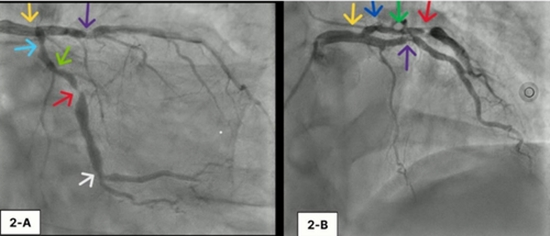

آقای ۵۸ ساله، دیابتی و سیگاری، سه سال پیش با تب، سرفه و تنگی نفس بستری شد. ابتدا فکر کردند فقط کرونا دارد، اما روز دوم سکته قلبی تشخیص داده شد و اکو نشان داد سوراخ بزرگی (۱۸ میلی‌متر) در دیواره بین بطن‌ها ایجاد شده است. چون وضعیتش خیلی بد بود، همان روزها جراحی اورژانسی بای‌پس عروق + ترمیم سوراخ انجام شد. بعد از ۴۵ روز مرخص شد و همه چیز خوب به نظر می‌رسید.

سه سال بعد، فقط با تنگی نفس متوسط هنگام فعالیت به کلینیک آمد. در معاینه پزشک صدای غیرطبیعی (سوفل) شنید. اکوی معمولی (دید چهارحجره‌ای معمولی) کاملا طبیعی بود! اما وقتی تکنسین با زاویه خاص به عقب (posterior tilt) قلب را نگاه کرد، ناگهان مشخص شد: دیواره بین بطن‌ها باد کرده و در محل ترمیم قبلی، یک سوراخ کوچک باقی مانده است که خون از چپ به راست می‌رود. همراه آن یک آنوریسم (برآمدگی ضعیف) هم وجود داشت.